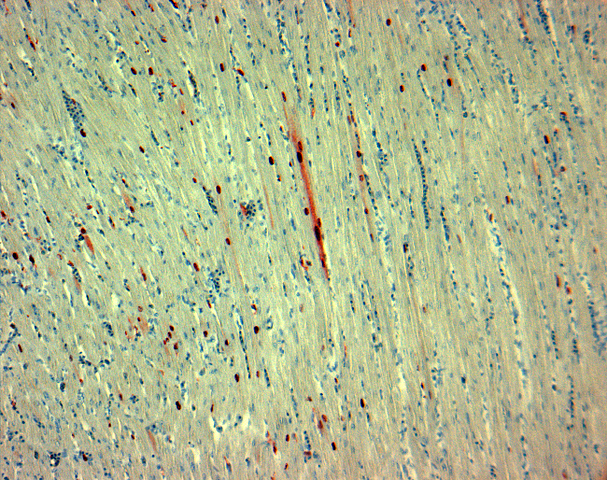

• Ziehl y Neelsen: tinción diferencial AAR

Ziehl y Neelsen: tinción diferencial AAR